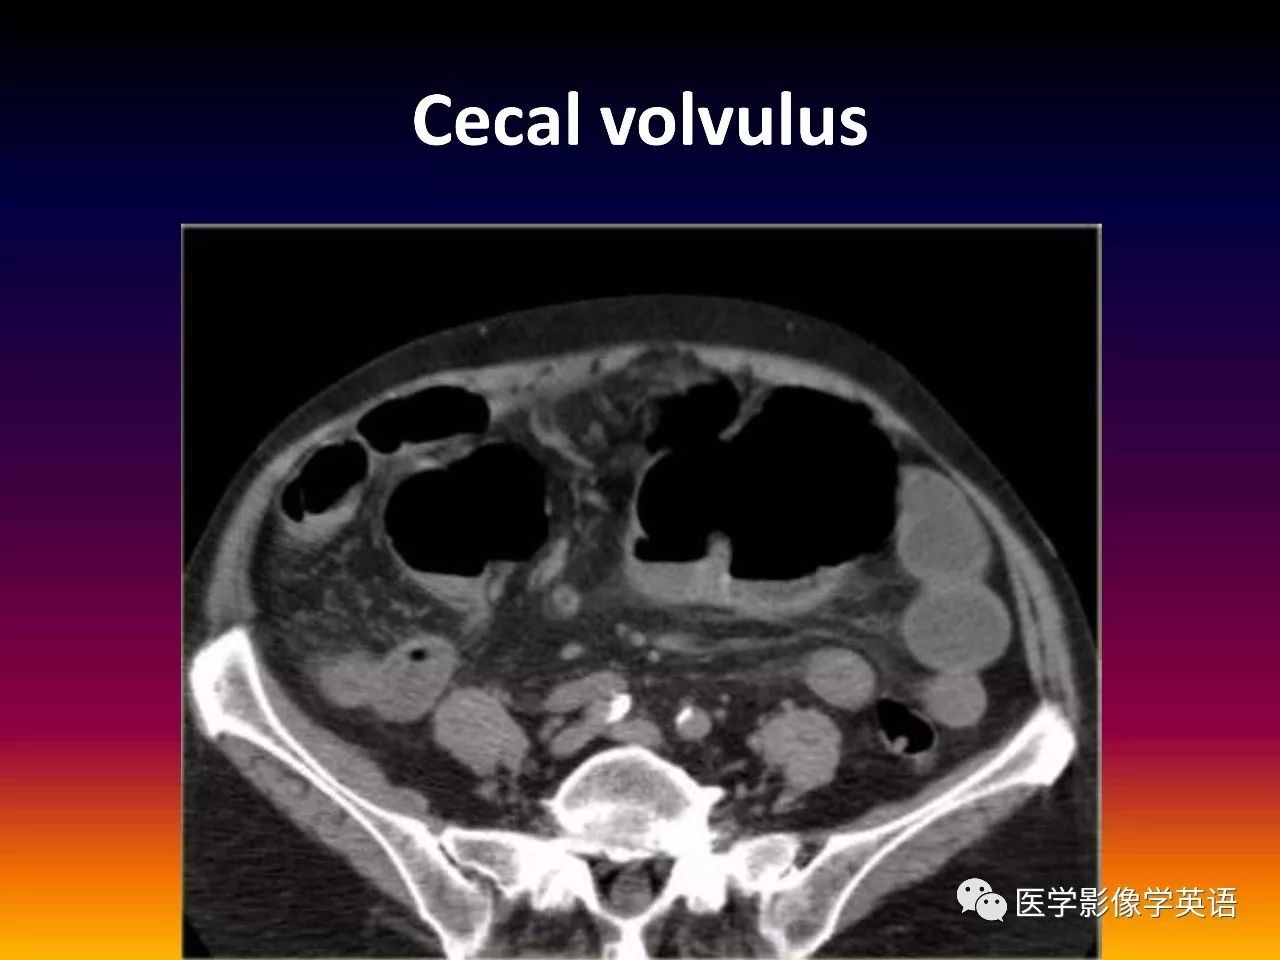

93. Cecal volvulus

94. Cecal volvulus

95. Cecal volvulus

96. Cecal volvulus

97. Cecal volvulus

98. Cecal volvulus

99. Cecal volvulus

100. Cecal volvulus